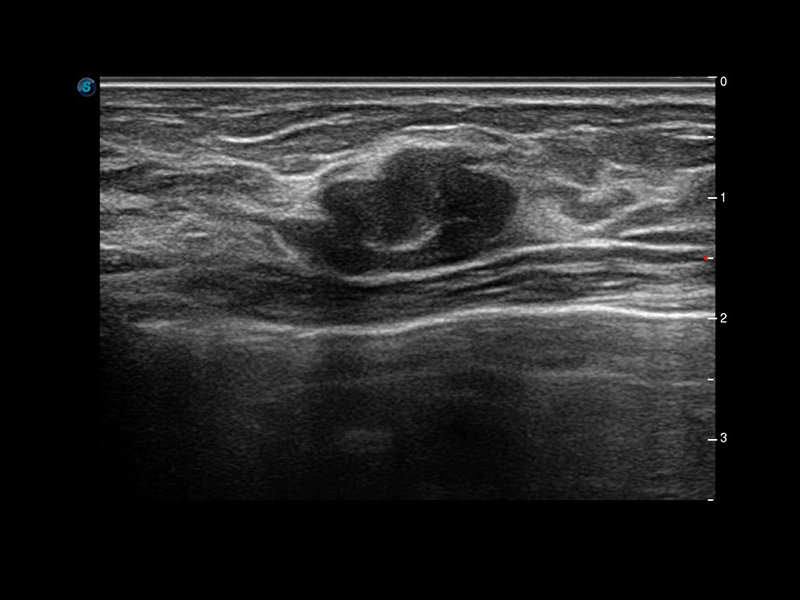

Micro F

Micro F bietet eine innovative Methode, um den sichtbaren Fluss in der Ultraschallbildgebung zu erweitern, insbesondere um den langsamen Fluss kleiner Gefäße sichtbar zu machen. Durch die Verwendung eines fortschrittlichen adaptiven Filters und die Akkumulation von zeitlichen und räumlichen Signalen kann Micro F den geringen Blutfluss effektiv von der Bewegung umgebendem Gewebe unterscheiden und die Hämodynamik mit höherer Empfindlichkeit und räumlicher Auflösung darstellen.

• Zervikales schlecht differenziertes Karzinom mit Micro F